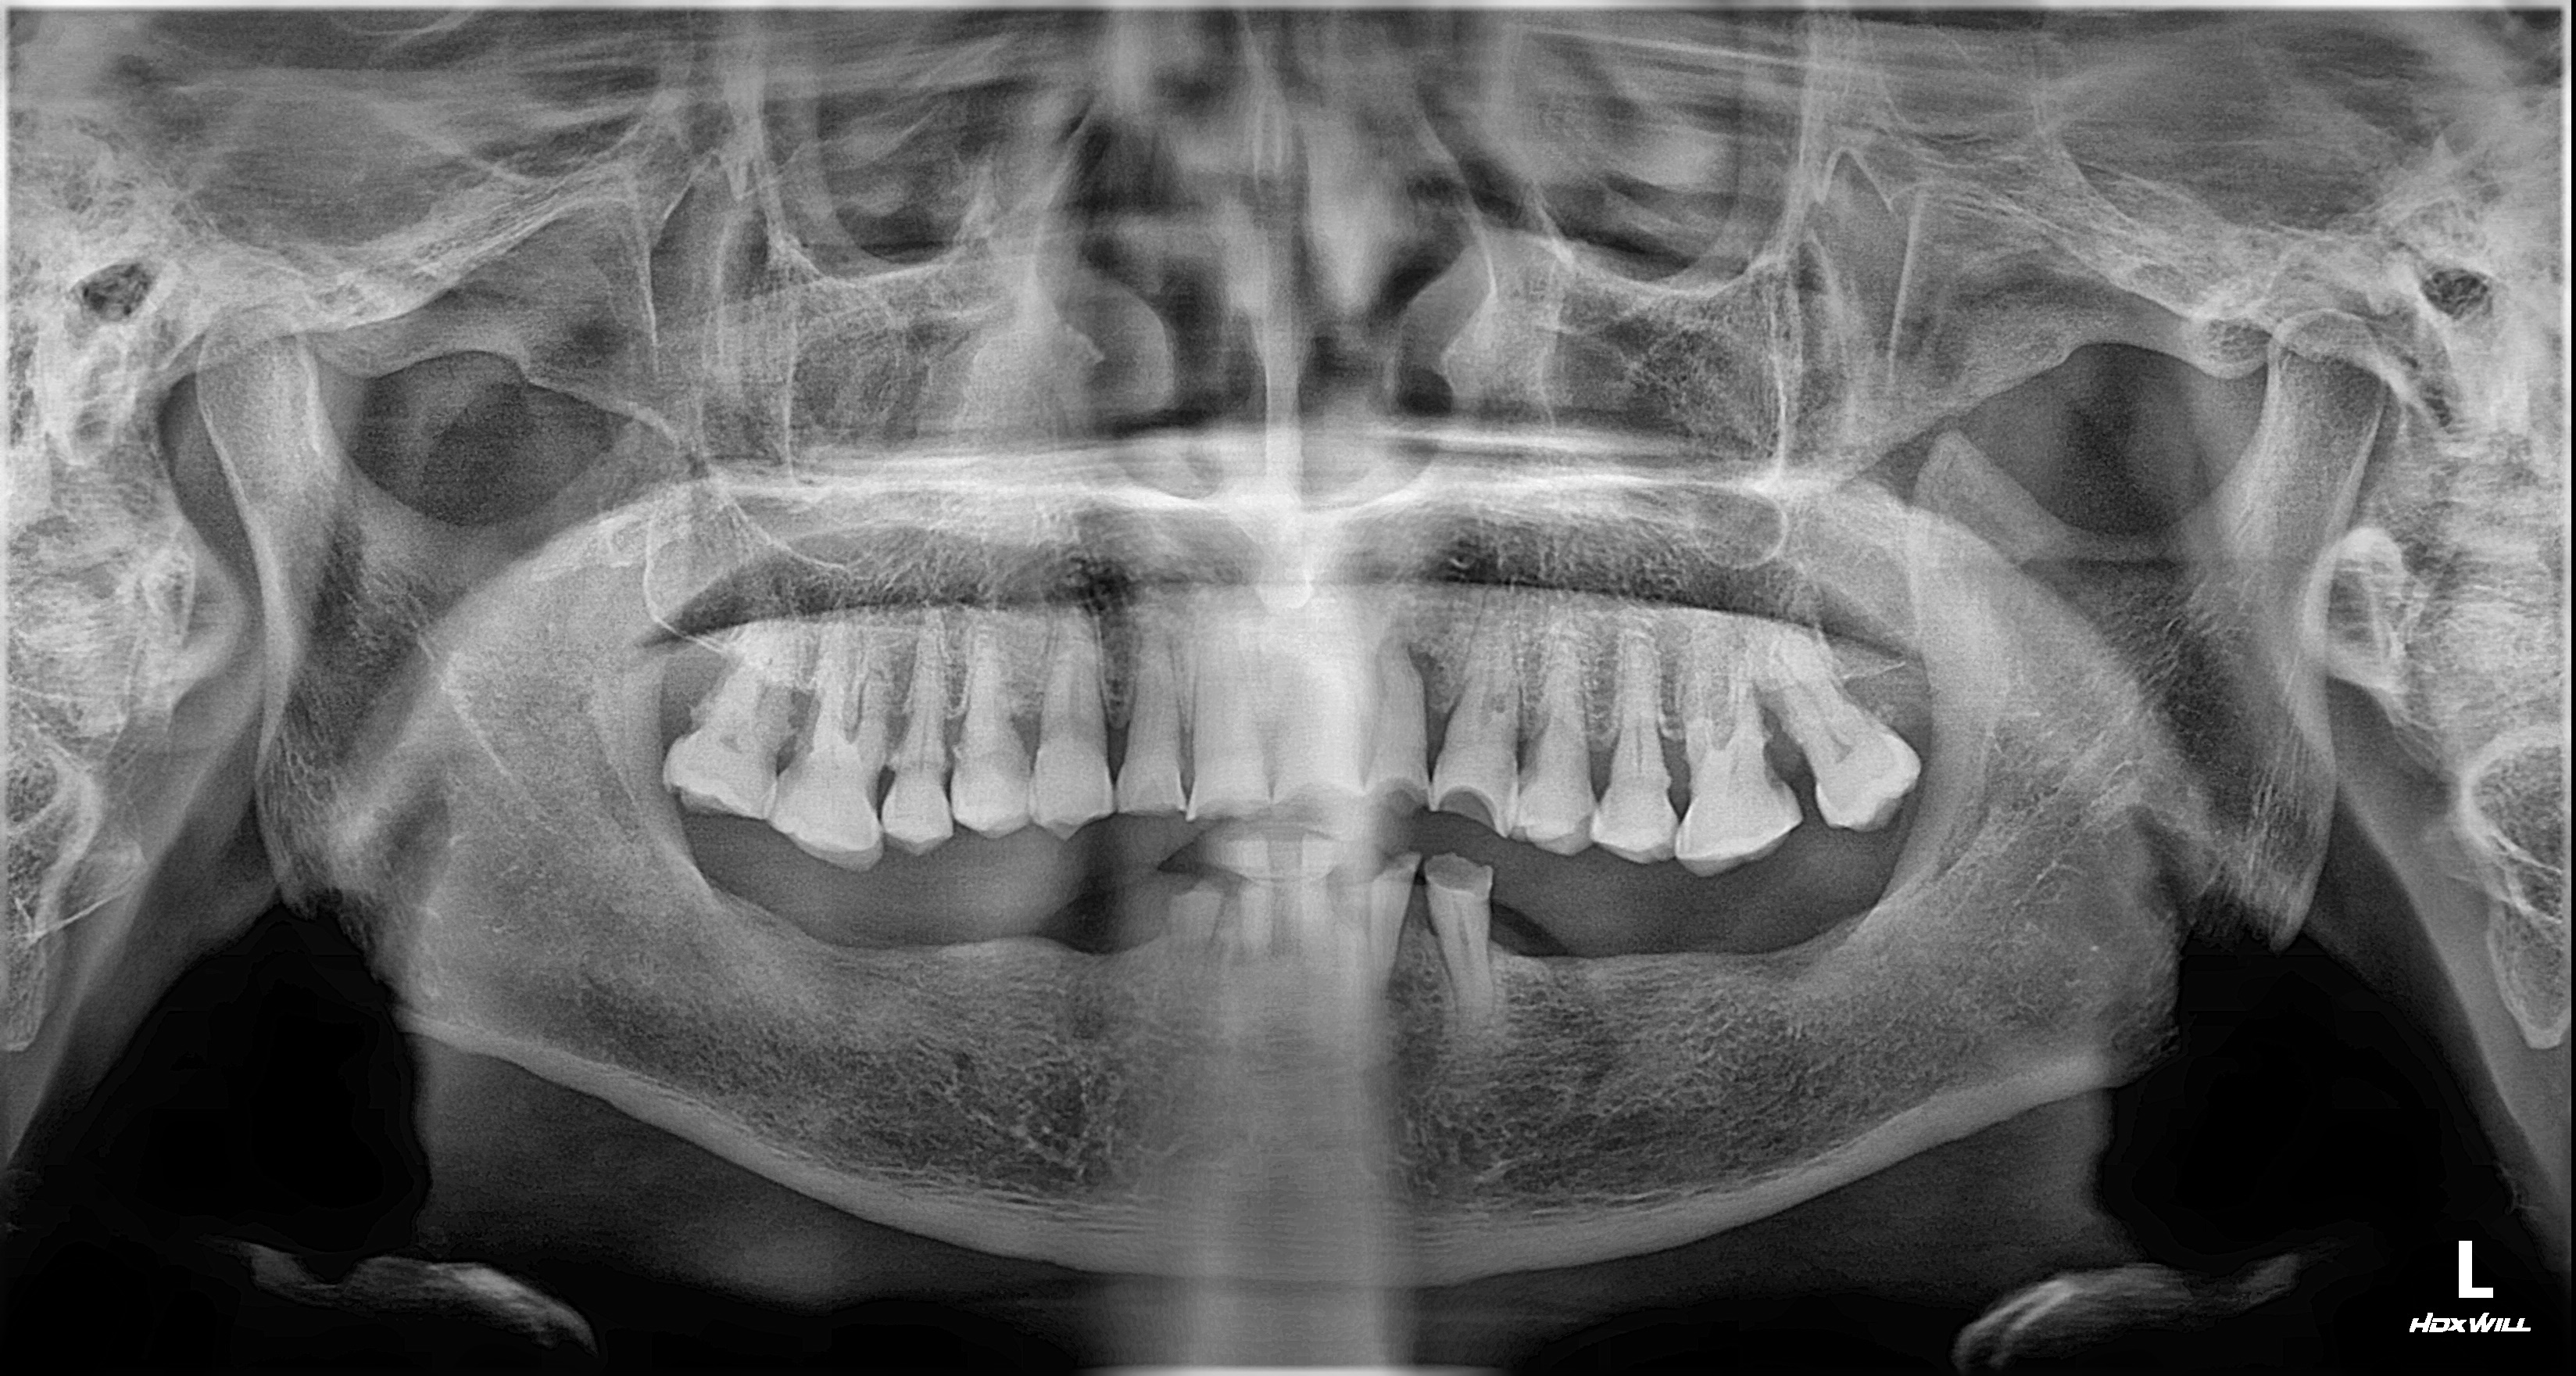

촬영일시: 2024.10.05.